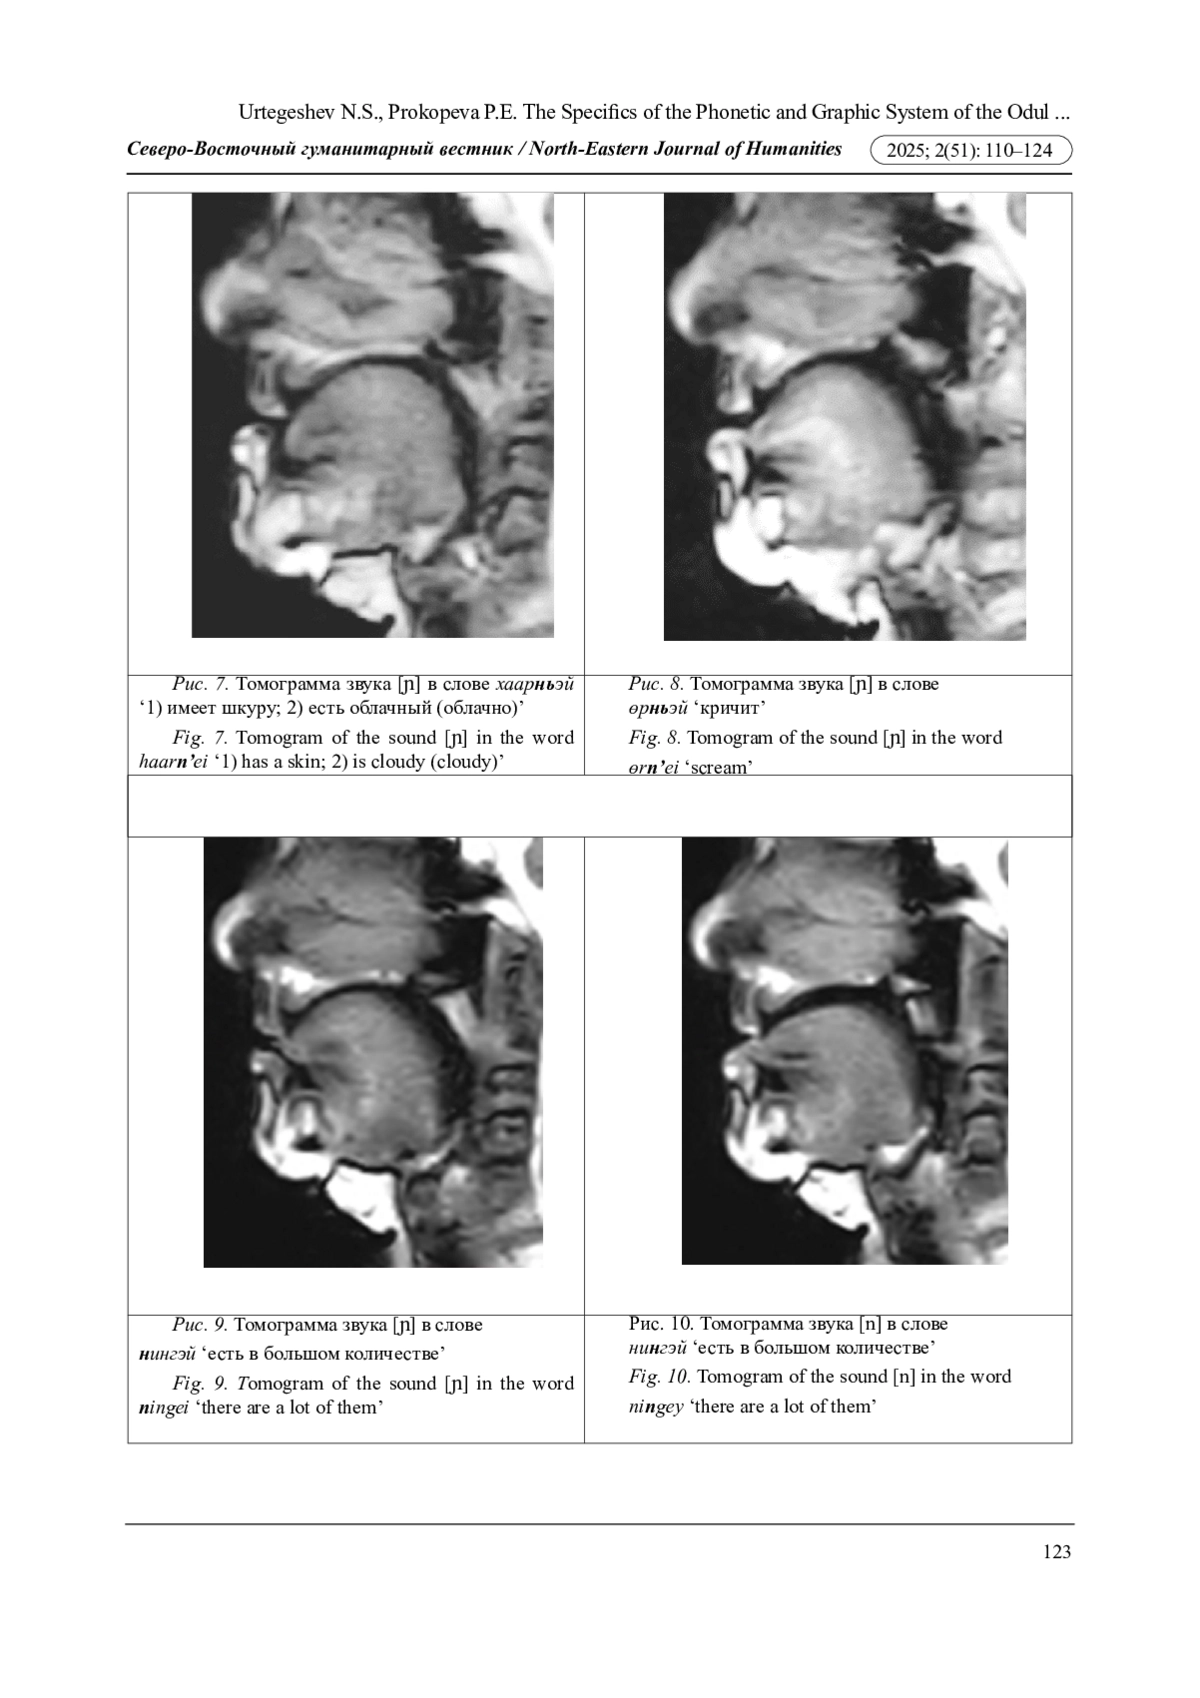

В настоящей работе впервые методами экспериментальной фонетики описываются артикуляционно-акустические характеристики мягких согласных лесного юкагирского, или одульского, языка, обозначаемых на письме Н(ь)1 и НЬ. В ходе анализа лингвистического материала получены следующие результаты: 1) монографом Н(ь) и диграфом НЬ обозначается одна и та же артикуляционная настройка [нOѴ] - мягкая, переднеязычно-среднеязычная фарингализованная, сильнонапряженная; 2) в одульском языке смычные назальные фронтальные (переднего образования) типа «<» противопоставлены не как в русском языке - переднеязычные твердые / переднеязычные мягкие, а переднеязычно-среднеязычные мягкие / переднеязычные интердентальные твердые.